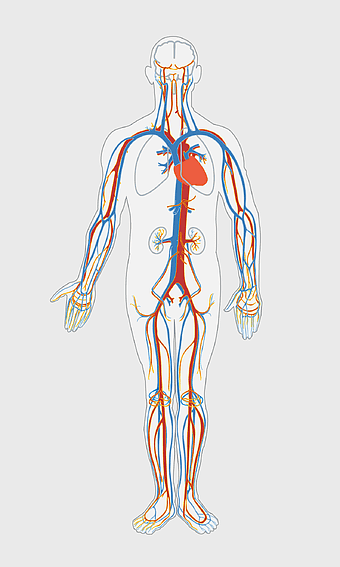

human circulatory system diagram, blood vessel network illustration, human anatomy chart, cardiovascular system overview, human body medical illustration, physiological system depiction, organ function visualization -

blue human anatomy illustration, human circulatory system diagram, digital human skeleton image, electric blue medical figure, human nervous system visualization, human body organ map, human health care graphic -